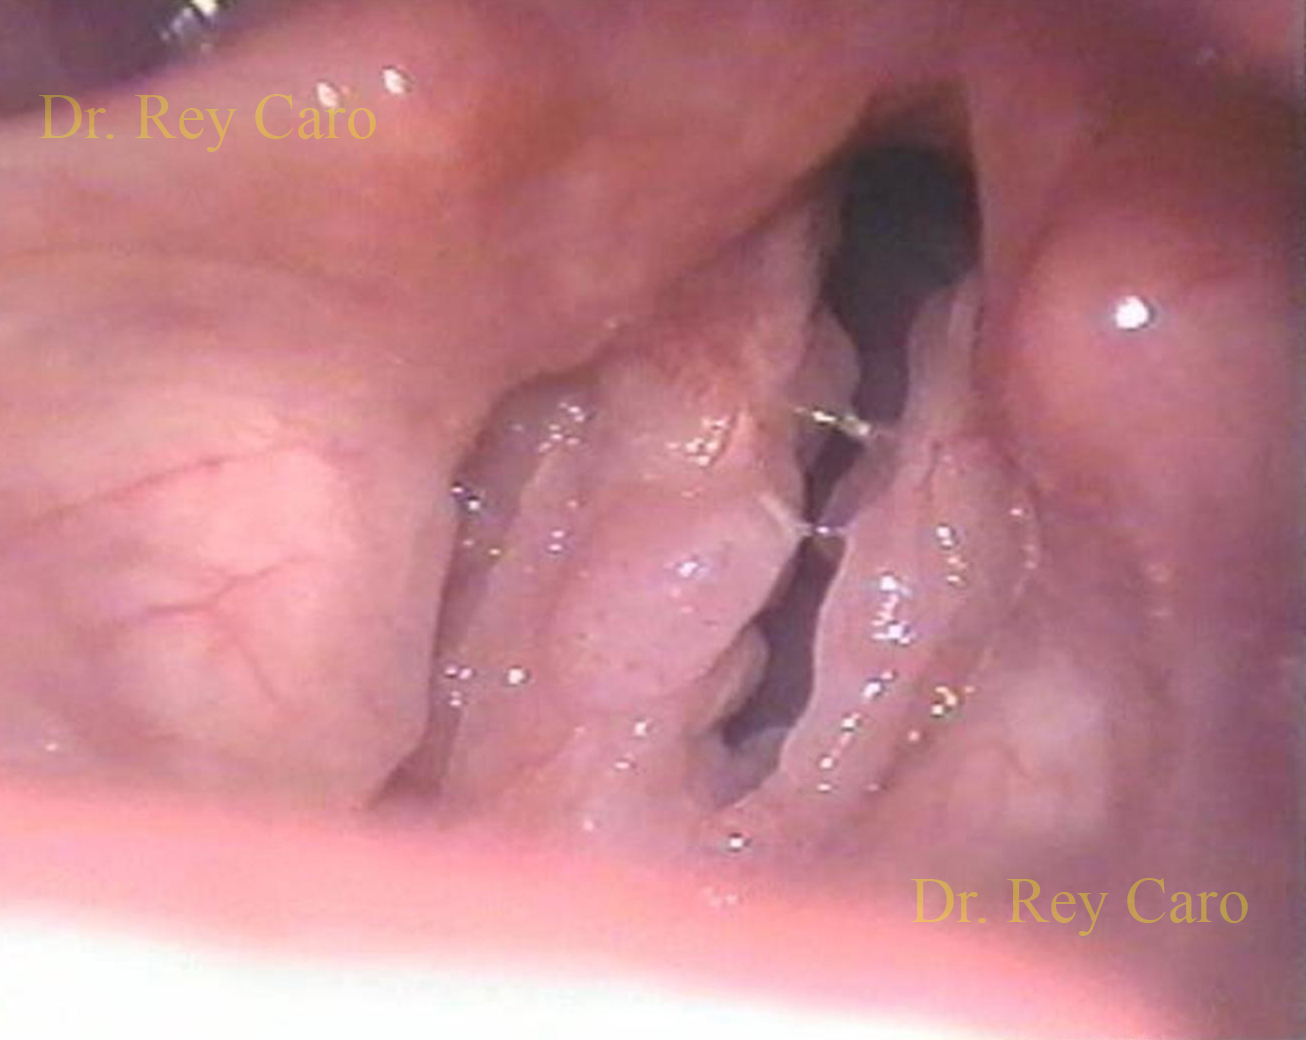

Papilomatosis en ambos pliegues vocales y si equis laríngea anterior por historia de cirugías previas. Papillomatosis of both vocal folds and a anterior comissure sinequiae.